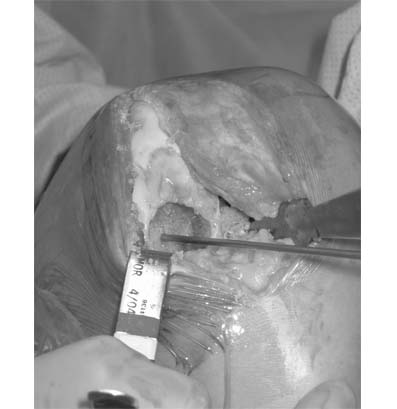

4.Due to the location of the lesion, an open mosaicplasty with one plug is selected as our treatment choice. The harvesting tool is placed within the lesion removing the plug with the damaged cartilage. On the image on the right, the inside of the recipient site is inspected with the arthroscope.

3.The posterior aspect of the defect is prepared to a precise depth with a specialized cutting device in a cylindrical fashion.

4.A second recipient site is created slightly farther forward on the end of the femur in order to span the entire defect.